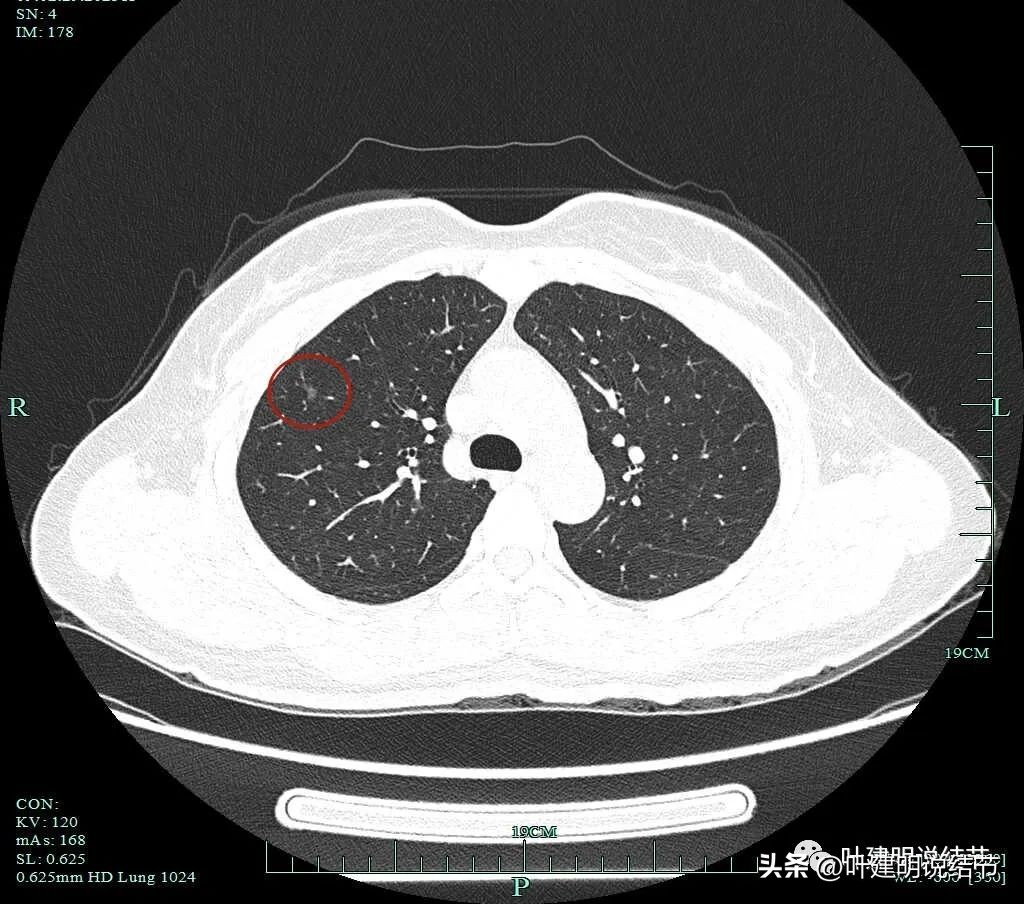

主病灶靶扫描重建影像:

蓝色箭头示月牙铲征;紫色箭头示毛刺或棘突征;桔色箭头示有血管进入并穿行与异常增粗;红色箭头示病灶轮廓与瘤肺边界清楚。

黄色箭头示病灶处有空腔征;粉色箭头示病灶内有实性成分;紫色箭头示毛刺征;绿色箭头示磨玻璃成分轮廓清,有毛刺。

砖色箭头示病灶有分叶征;蓝色箭头示胸膜牵拉;紫色箭头示毛刺征;红色箭头示整体轮廓与瘤肺边界清。总体上看病灶有收缩力、有分叶与毛刺,而且灶内密度不均。是较为典型的浸润性腺癌影像表现。

病灶毛刺、边界、空泡、胸膜牵拉等征象。

上图见病灶有明显血管弯征以及血管走向病灶并进入。

病灶外形不规则,有收缩力与血管走向病灶。

密度不均、空泡征、磨玻璃成分、胸膜牵拉以及整体轮廓清。

病灶与胸壁间感觉像阻塞性炎性,或肿瘤延伸向胸膜侧(密度显得有点低)。

连续区有多支血管走行。

病灶混合磨玻璃密度,轮廓与边界清,毛刺明显,灶内密度杂乱,部分边缘毛刺明显。

血管进入、密度不均杂乱、表现不平、胸膜牵拉影响、灶内实性成分。